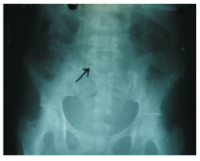

Kidney Stone In A 7-Year Old Girl

Dr. A. A. Olatunji, A. F. Adekanmbi, T. A. Ogunlesi, M. B. Fetuga (Author)

41-44